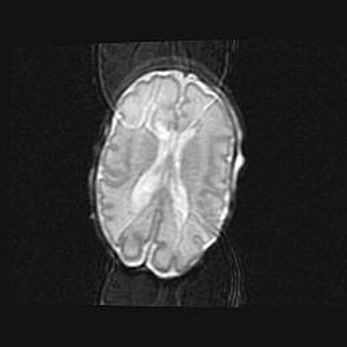

Лейкомаляция с кистозно-глиозной дегенерацией головного мозга.

Возраст: 2 месяца 25 дней

Вес: 6400 г

Окружность головы: 40 см

Срок гестации: 41 неделя

Лейкомаляцию относят к ишемически-гипоксическим повреждениям головного мозга, диагностируемым у новорожденных. При лейкомаляции в головном мозге обнаруживают очаги некроза, возникшие после тяжелой гипоксии и нарушения кровотока. В процессе морфогенеза очаги проходят три стадии: 1) развития некроза, 2) резорбции и 3) формирования глиозного рубца или кисты. Перивентрикулярная лейкомаляция (ПЛ) встречается примерно в 12% случаев среди новорожденных, обычно – у недоношенных детей, причем, частота ее зависит от массы, с которой младенец появился на свет. Наибольшее число малышей страдает лейкомаляцией, если масса при рождении 1500-2500 г.